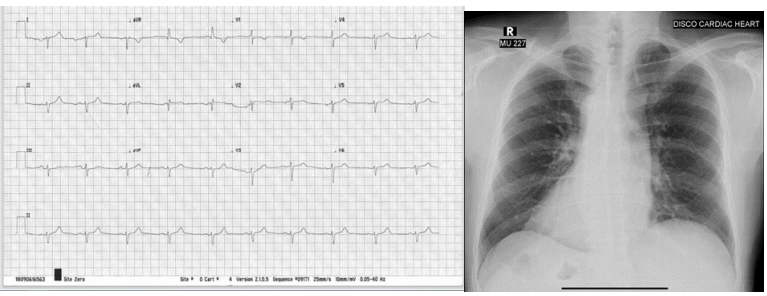

55 year old male known case of Hypertension presented to the Cardiology Clinic at Tabba Heart Institute with complains of chest pain that was central, aggravated on exertion and relieved at rest, initially CCS 2 in intensity but worsened to CCS 3 over the past 10 days. The ECG done showed Extreme right Axis Deviation, with upright P wave R wave in aVR. It also showed prominent R wave in lead V1 with poor R wave progression. All findings suggestive of dextrocardia.

Figure 1